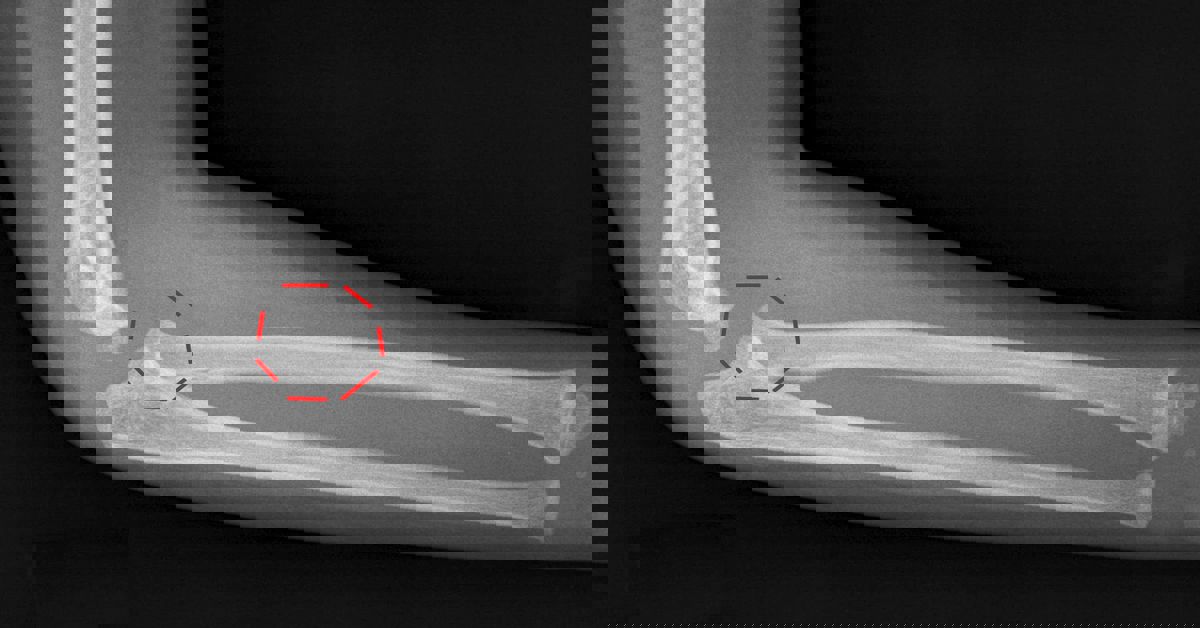

Önkol kemiklerinin dirsek eklemindeki ayrılarak yer değiştirmesiyle oluşur. Dirsek; üst kolda bulunan humerus ile ön koldaki radius ve ulna kemiklerinden oluşur. Bu üç kemiğin uyum içinde hareket etmesini sağlayan güçlü bağlar, kapsül yapıları ve kaslar bulunur. Travma sonucu bu uyum bozulduğunda eklem bütünlüğü kaybolur ve çıkık meydana gelir. Bu noktada birçok kişi dirsek çıkığı nedir? sorusunu merak eder, çünkü yaralanma anında ortaya çıkan ağrı, şişlik ve şekil bozukluğu oldukça belirgindir.

Dirsek eklemini oluşturan kemiklerin doğal hizasından ayrılmasıyla oluşan bir yaralanmadır. Dirsek, günlük hayatta sık kullanılan bir eklemdir. Bu nedenle düşme veya ani bir darbe sonrası kolayca zarar görebilir.